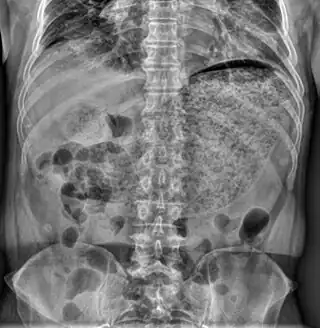

La gastroparesia es un trastorno estomacal, en el cual el estómago sufre una parálisis que incrementa demasiado el tiempo que tarda en vaciar su contenido. Ante la presencia de gastroparesia, el estómago no puede contraerse normalmente, y por lo tanto, no es capaz de degradar los alimentos ni propulsarlos hacia el intestino delgado en forma adecuada.